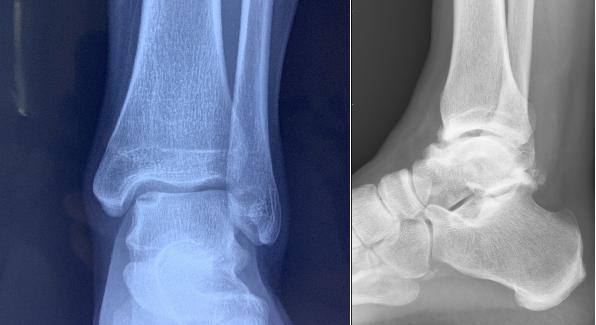

踝关节,主要由 3 块骨头组成:胫骨(下肢的主要负重骨)、腓骨(下肢的次要负重骨及韧带、肌肉的附着区)、距骨(足的第二大骨)。

参考上图,我们可以将人的踝关节想象成一个正在骑马的人,胫骨和腓骨就像是人的两条腿一样,骑跨在有着「马鞍」一样关节面的距骨上。

从 X 光片上,我们只能看到踝关节的骨性的结构,这也是为什么有时候医生会要求再做核磁共振的检查来看看踝关节的周围,韧带、肌肉以及肌腱的情况。